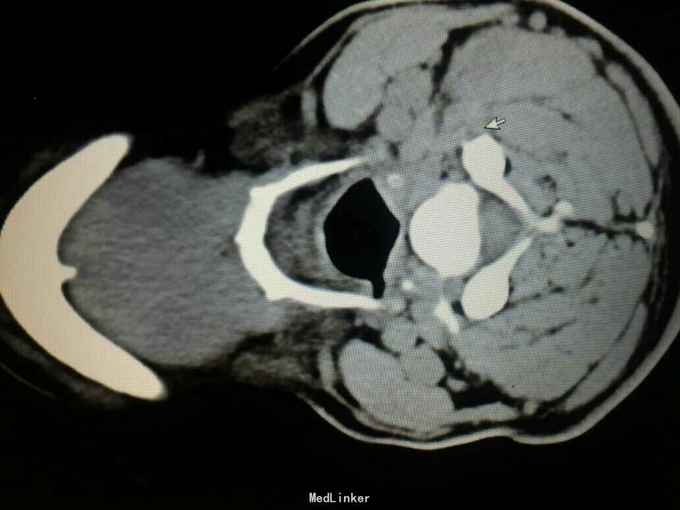

专科检查:颈部左侧胸锁乳突肌后缘中点可触及一大小约1.5×2.0cm肿物,类梭型,界清,质硬,无疼痛,活动度良好。 颈部CT及核磁检查

诊断:颈部左侧纤维瘤病。全麻下行:颈部左侧肿物切除术+神经移植术(备)。术中探查肿物与臂从神经界限清,排出神经纤维瘤可能,考虑肌肉来源肿瘤。